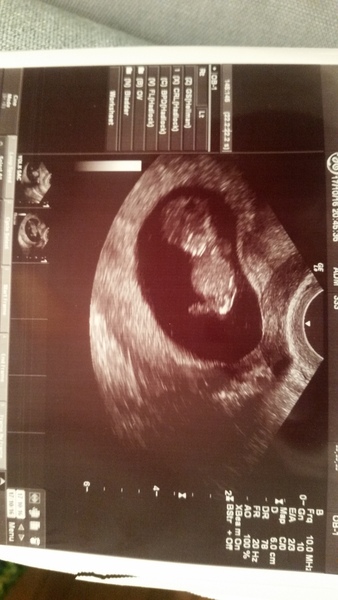

Fox, we ended up having a private scan a few weeks back. I thought the TWW was bad until we got pregnant and started waiting for the scan! I'd messed work about so much, I felt that I needed to tell them, but wanted to see that all was progressing as planned first... and on that note, great pic, Niks. They grow so much in the run up to the 12-week scan, don't they? Can't wait for ours next week!